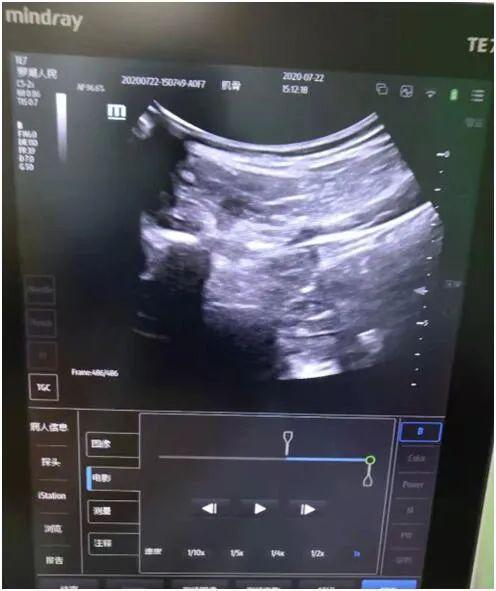

超声引导下神经根阻滞

神经阻滞是急性带状疱疹性神经痛最好的治疗方法,具有迅速镇痛、改善局部血液循环、促进愈合、预防发生带状疱疹后遗神经痛等有点。

超声+X线双引导下椎间孔脊神经脉冲射频微创介入手术